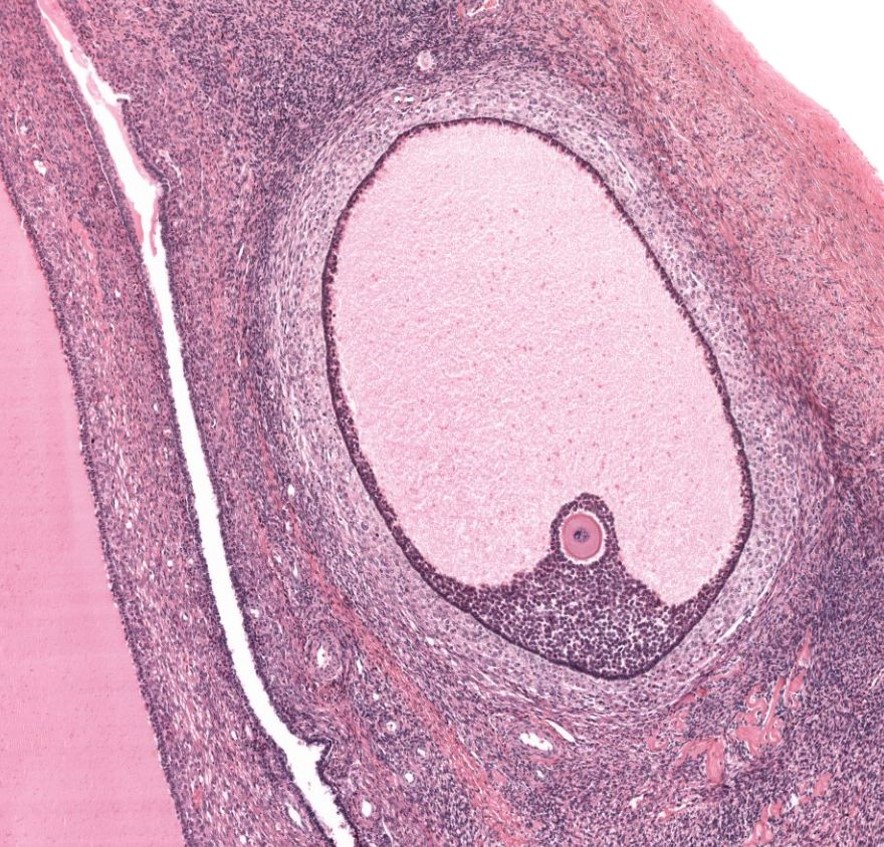

Ovário - folículo de Graff